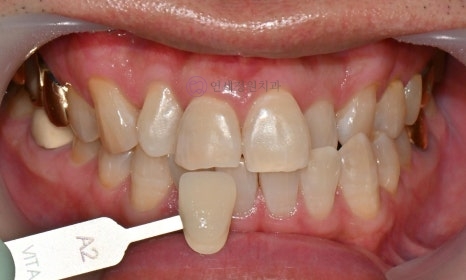

Before starting the teeth whitening process, the color of your teeth will be assessed. A shade guide will be used to record the tooth color; the shade guide is a specific indicator that expresses the degree of lightness or darkness of the teeth in stages. As the letters increase numerically, the color becomes darker. Tooth colors are classified into 16 stages, ranging from B1 to C4 (B1-A1-B2-D2-A2-C1-C2-D4-A3-D3-B3-A3.5-B4-C3-A4-C4). The closer to B1, the brighter the natural tooth color, and the closer to C4, the darker the color.

Before and After

Before Shade: A3.5 / After Shade: A2

Before Shade: A2 / After Shade: B1